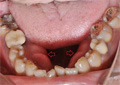

![]() |

楔上欠損が多く見られます。 |